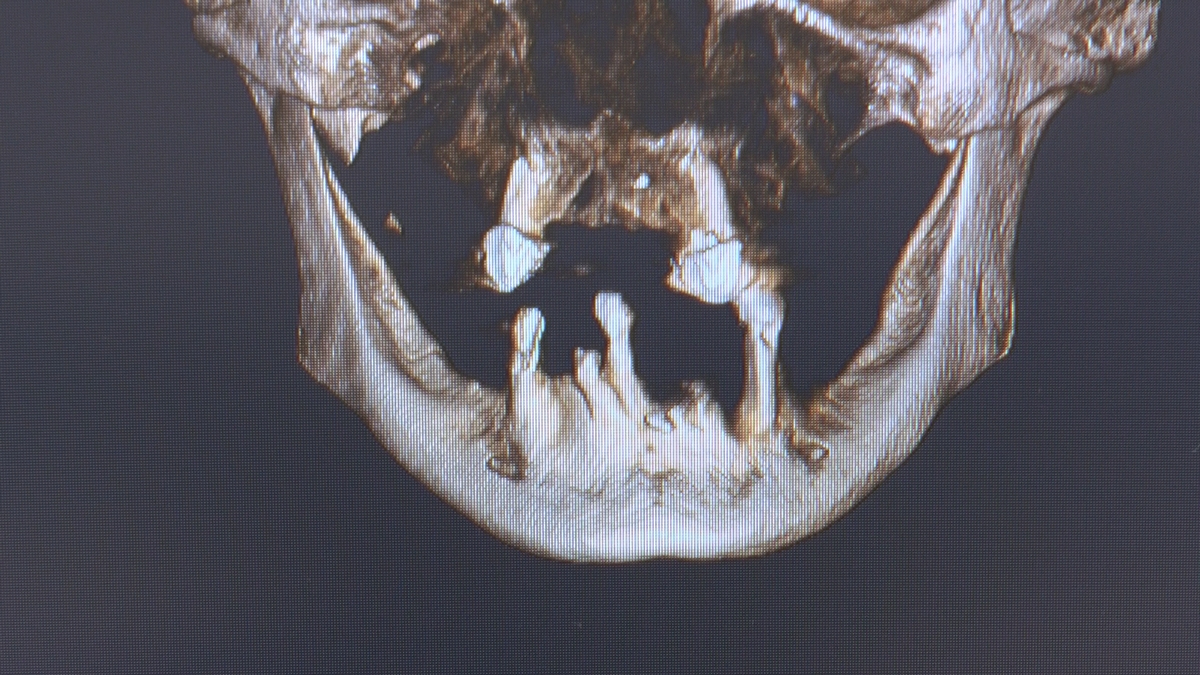

Wprowadziliśmy łącznie 25 implantów w tym wykonaliśmy:

dwa zabiegi All- on -4 / jeden w szczęce, jeden w żuchwie/ z usunięciem zębów i natychmiastową implantacją oraz natychmiastową odbudową protetyczną